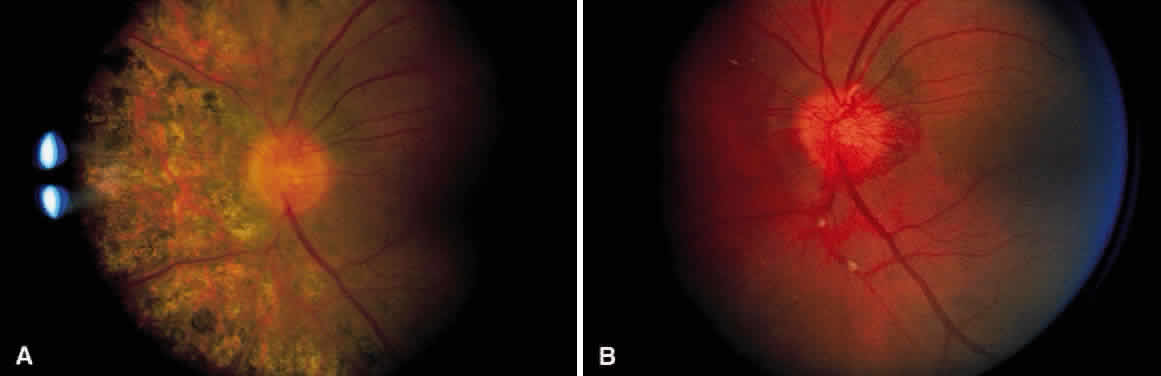

As a result of the retinal nonperfusion, new vessels can form either on the disc (neovascularization of the disc) or, more commonly, neovascularization can occur elsewhere in the retina (Fig. 5). These abnormal blood vessels can hemorrhage and are the major cause of visual loss in this disease. The neovascularization in the peripheral retina usually occurs at the junction of perfused and nonperfused retina, similar to the appearance of neovascularization in the peripheral retina in diabetic retinopathy and the other peripheral proliferative retinopathies. Neovascularization can be associated with extensive fibrovascular proliferation and fibrosis (Fig. 6). The anteroposterior and tangential traction resulting from the fibrovascular proliferation places these eyes at risk for development of retinal detachment. Neovascularization of the iris also has been described.